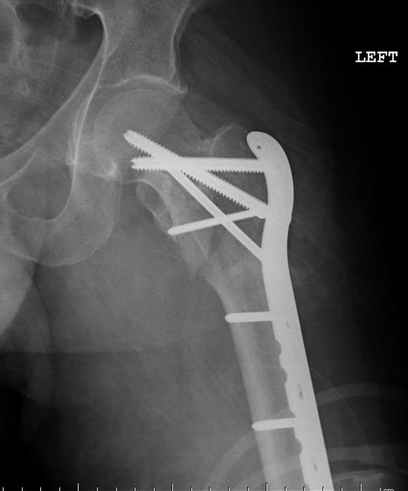

Применили проксимальную Synthes Locking plate, из-за множественных фрагментов посчитали более приемлемым в этом случае (клиника университетская, резиденты должны имет возможность созерцать разные варианты остеосинтеза).

Также старался минимизировать доступ на уровне перелома с субвастус доступом, диафиз фиксирован перкутанно, не стали гонятся за малым вертелом, как смог зафиксировал.

Перелом из четырех фрагментов, не стабильный (лекция Michael R. Baumgaertner, http://www.hwbf.org/ota/bfc/baumg/exp.htm), нужна стабильная фиксация.

Фиксация таких нестабильных чрезвертельных и reverse obliquity субтрохантерик переломов всегда была сложной задачей и ранее использовали Blade Plate. Но многие локальные общие ортопеды, к которым, в основном поступают такие больные, имели трудности с применением импланта, где необходимо было точная калькуляция по введению Blade и поэтому Synthes разработал Proximal Locking plate как альтернативу, где три проксимальные шурупа в разных направлениях создают концепцию угловой стабильности Blade Plate.

Со второго дня движения в суставе, контрольный осмотр через две недели и в зависимости от рентгенологического сращения, дозированную нагрузку с постепенным увеличением начнем через 5-6 недель.